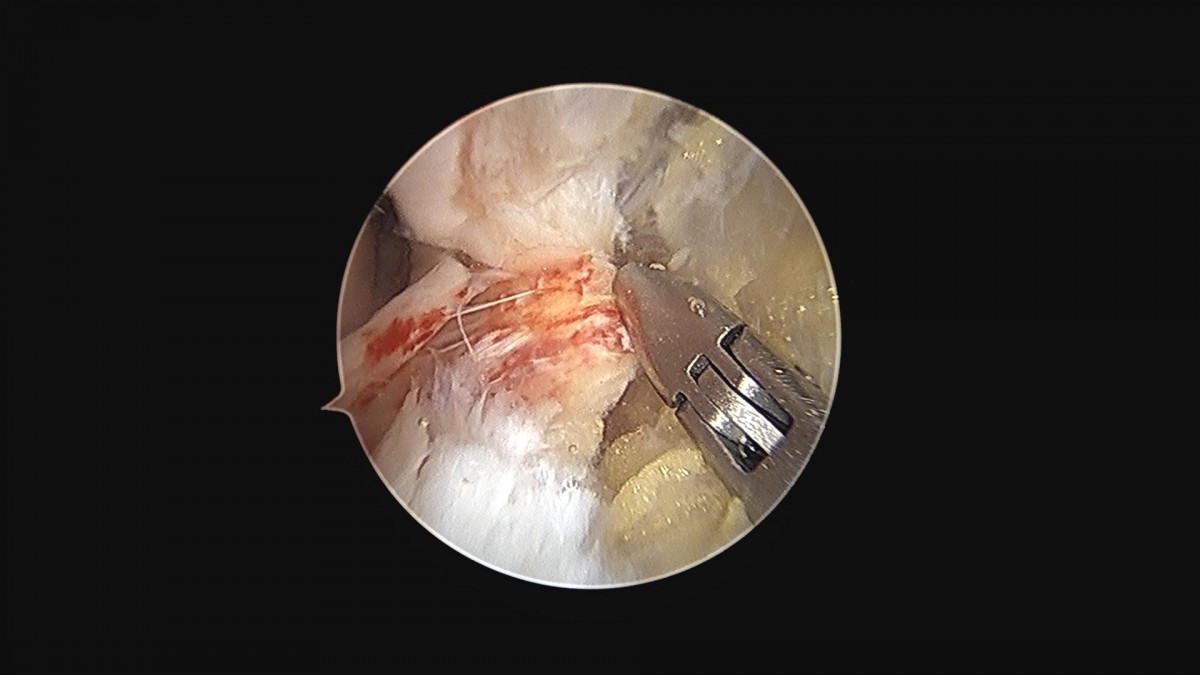

최원락원장님 발목 인대 봉합술 이남O 환자

작성자 최고관리자 댓글 0건 조회 1,660회 작성일 24-07-06 12:06